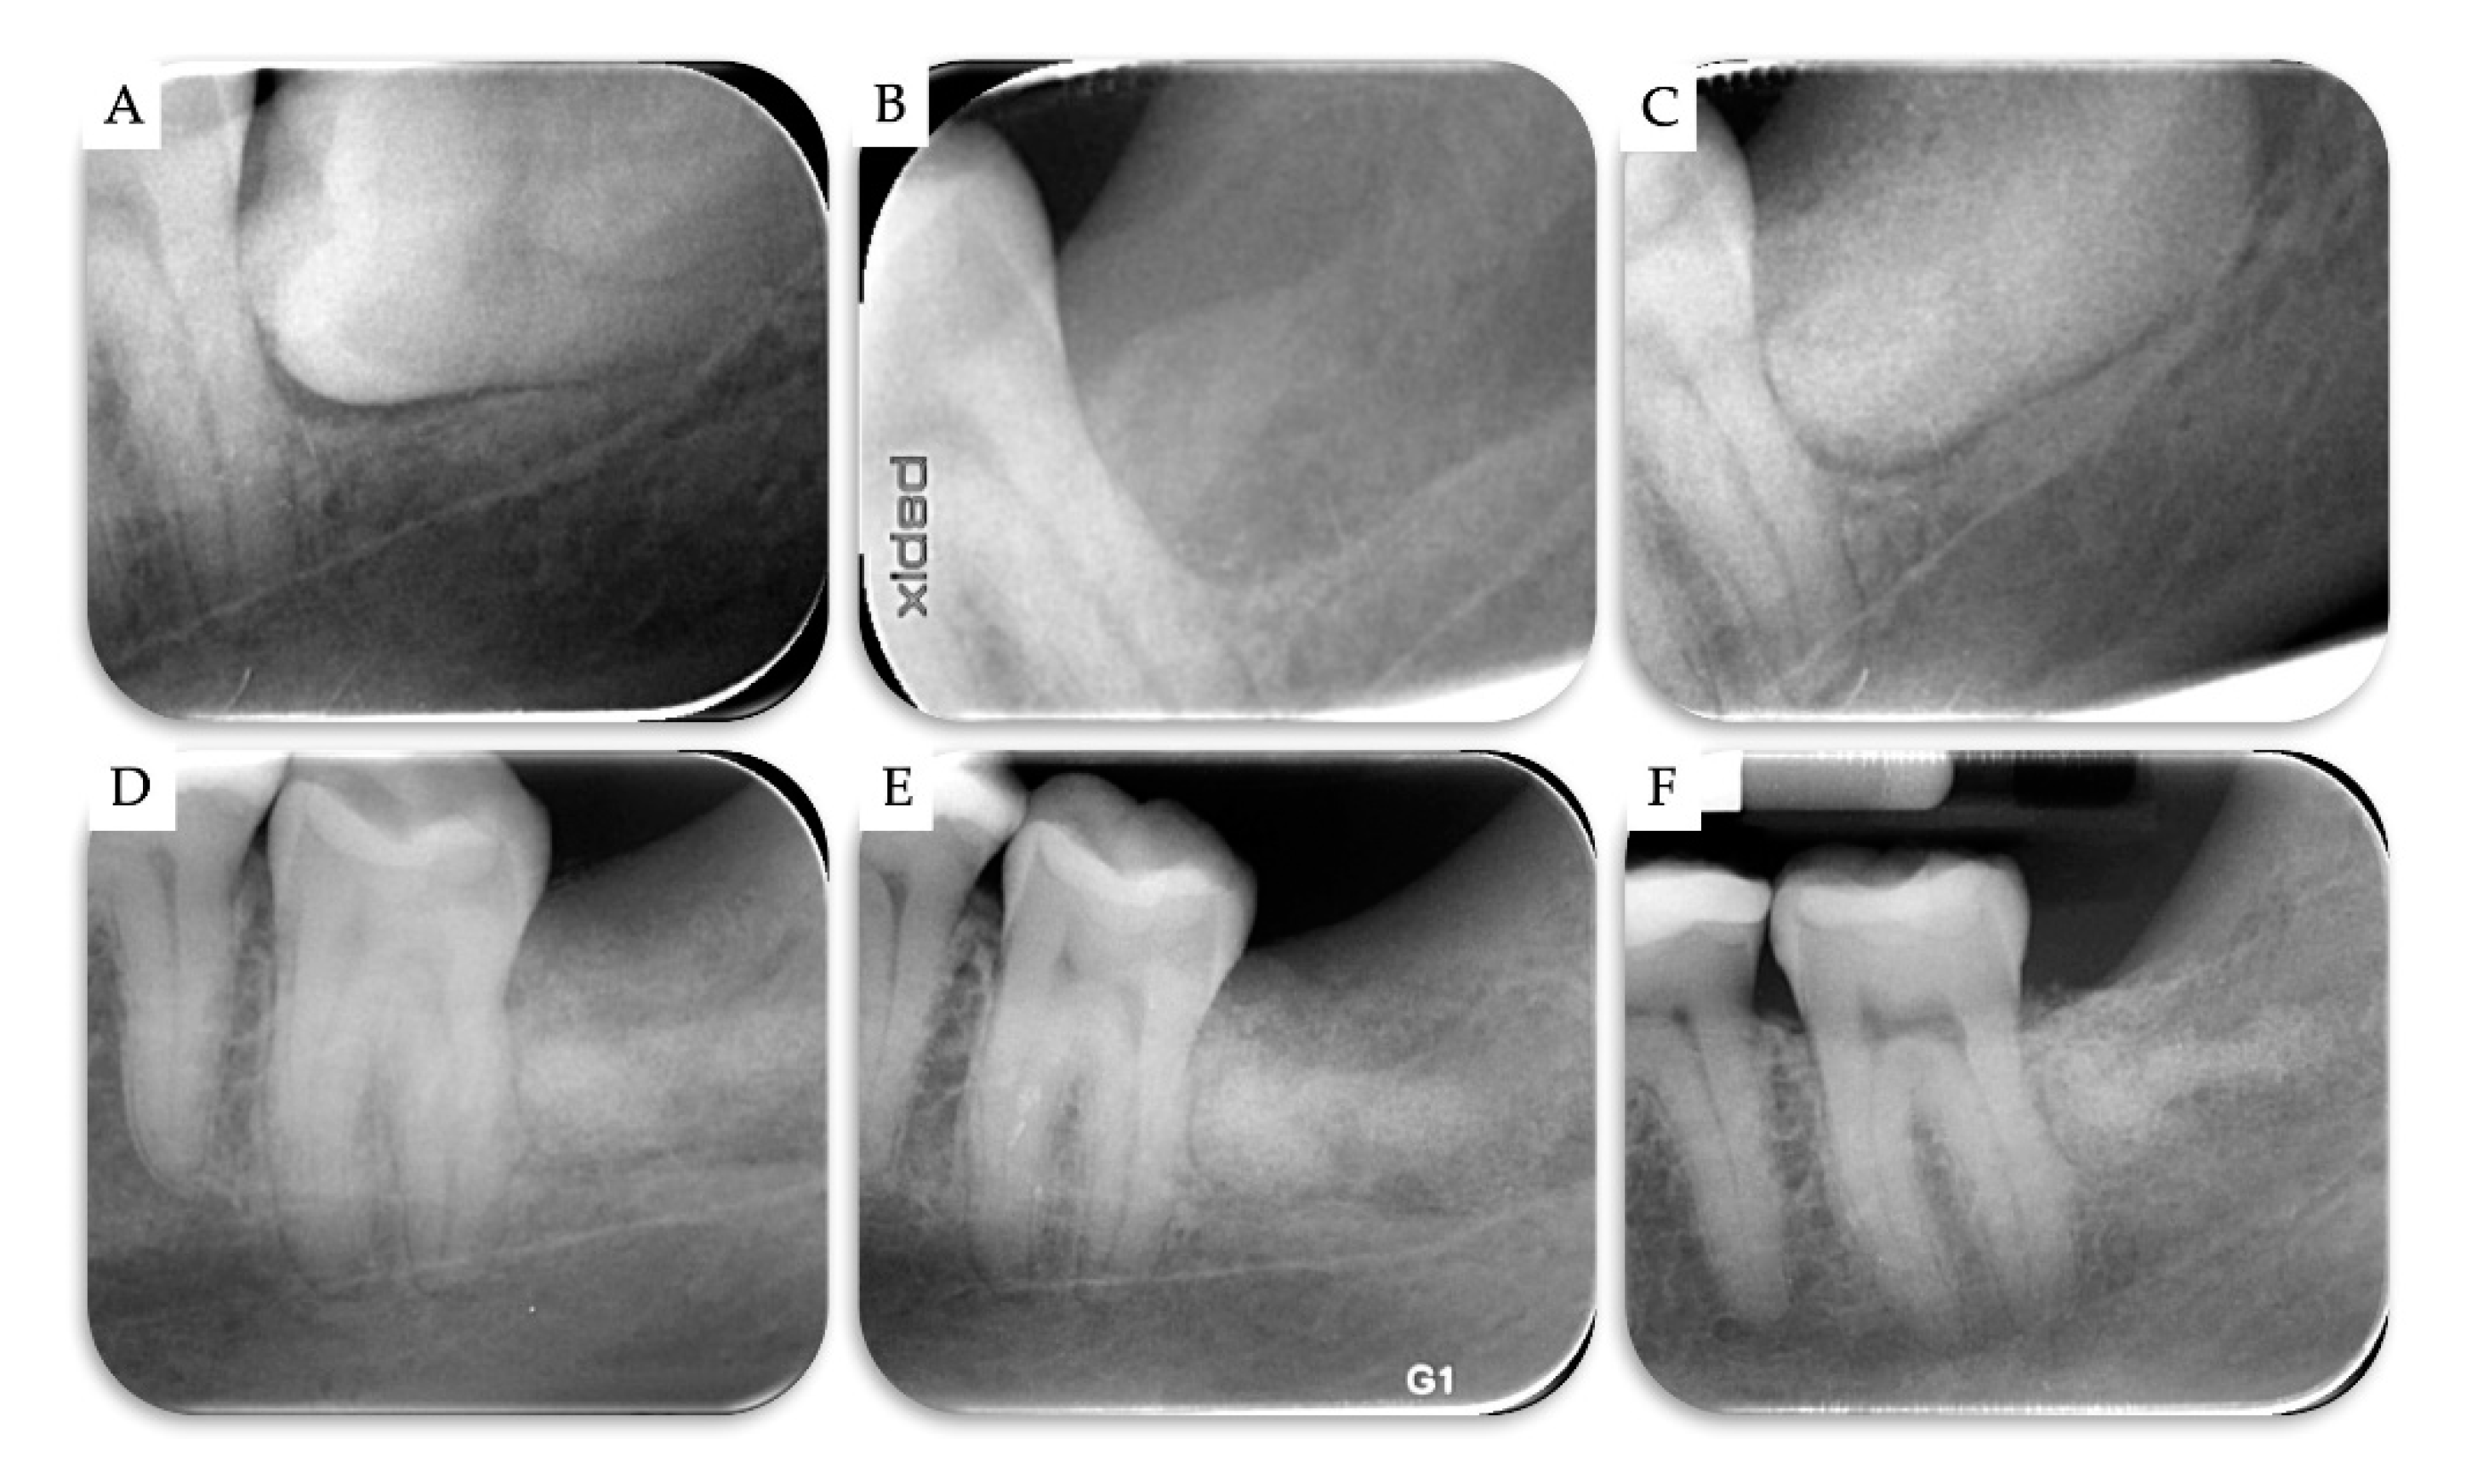

3. Results

| Case | Gender | Age | Smoker | M3 | Impaction | Follow-Up (years) | PD T0 (mm) | PD T1 (mm) | BD T0 (mm) | BD T1 (mm) | BG (mm) |

|---|---|---|---|---|---|---|---|---|---|---|---|

| 1 | F | 51 | No | 48 | Mesio-angular | 2 | 12 | 3 | 11.1 | 5.2 | 5.86 |

| 2 | F | 36 | No | 38 | Horizontal | 2 | - | 1 | 7.4 | 1.3 | 6.1 |

| 3 | M | 42 | No | 38 | Horizontal | 1 | - | 2 | 10.2 | 4.4 | 5.79 |

| 4 | M | 34 | No | 48 | Horizontal | 1 | - | 2 | 8.6 | 2.1 | 6.51 |

| Mean | 40.75 | 1.5 | 2.00 | 9.33 | 3.25 | 6.07 | |||||

| SD | 6.61 | 0.5 | 0.71 | 1.43 | 1.6 | 0.28 |